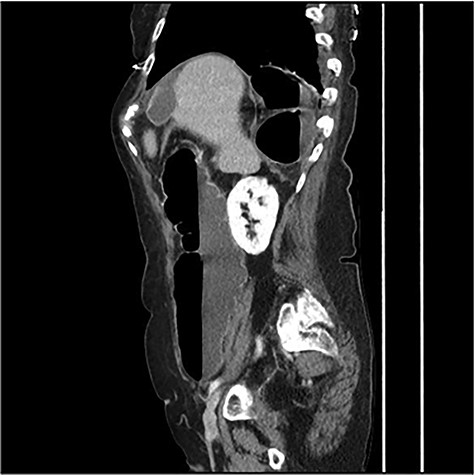

The scanner demonstrated a colonic occlusion resulting from an incarceration, which was diagnosed as a hernia of Bochdalek containing the hepatic angle of the colon (Fig. 2–4).

: CT scan images demonstrating a right diaphragmatic hernia containing intestine.

CT scan images demonstrating a right diaphragmatic hernia containing intestine.